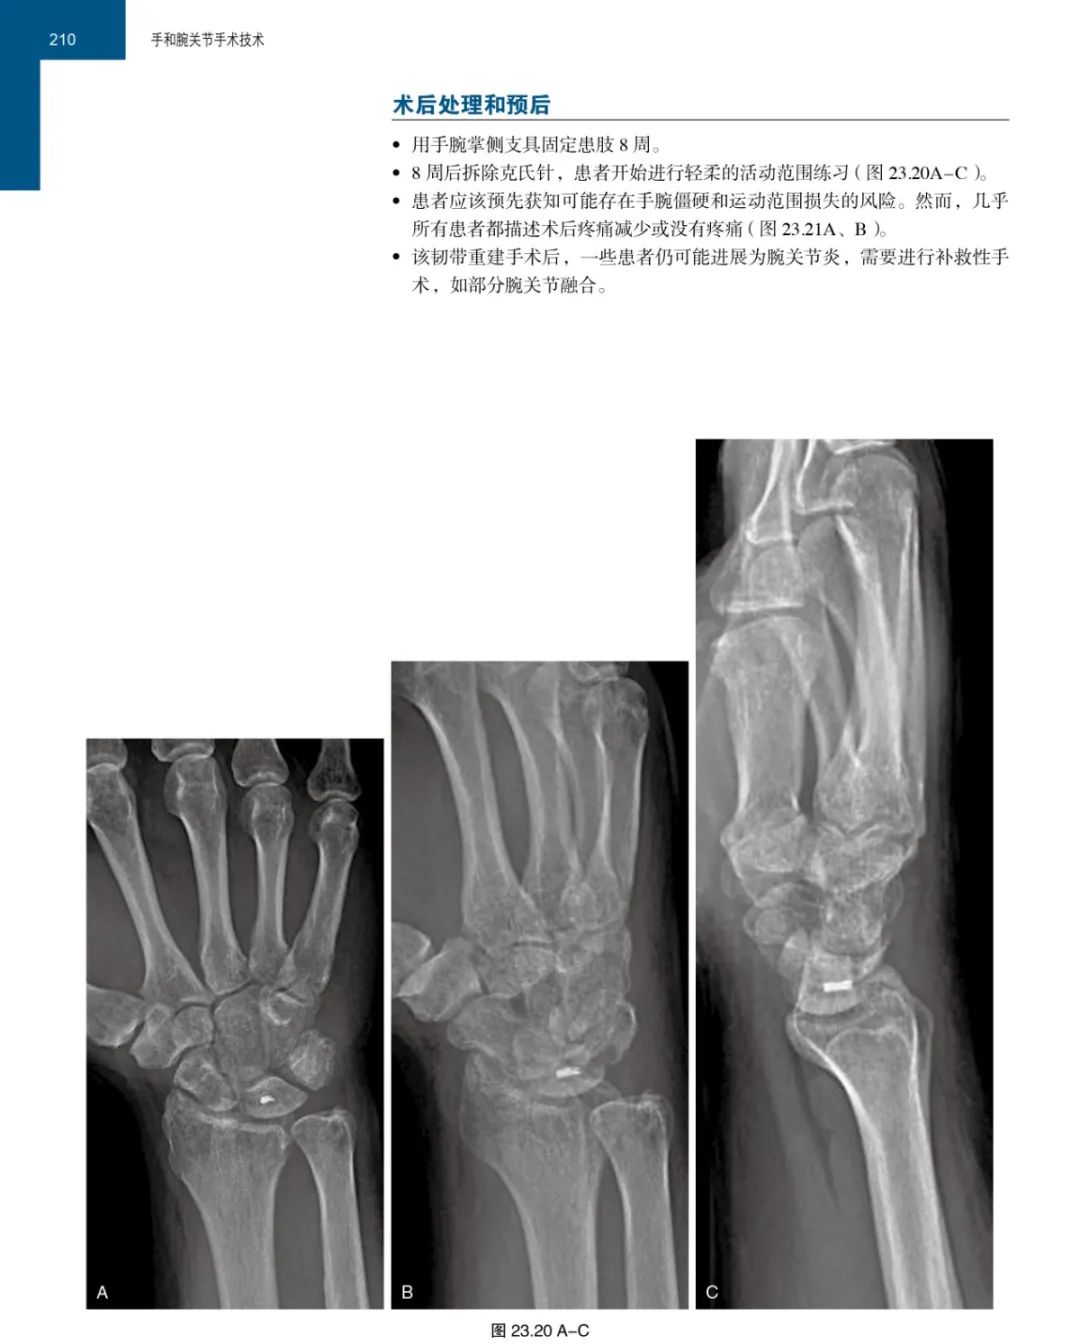

在本书的各章节中,对于当前手和腕手术的热点问题,如桡骨远端骨折与畸形愈合、腕关节镜、神经和肌腱移植、皮瓣与显微外科等都进行了清晰、准确且详尽的描述,能使每一位骨科医生受益匪浅。手术操作一目了然。手术的每一个操作都有清晰的手术图片,患者的病情和手术结果也都有放射影像图片。介绍病例有如身临其境。书中配有大量彩色手术照片以及标出主要解剖结构的示意图。有助于提高您的手术操作技能。